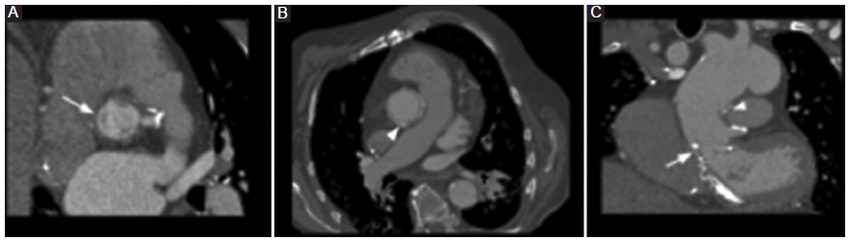

Los pseudocolgajos son visualizados como una banda lineal hipodensa generada por una leve angulación del injerto, en ocasiones confundido con una disección aórtica real, al no ser examinado en múltiples planos (Fig. 11) (8.

Por último, las áreas de realce u ocupación en el espacio generado entre la raíz del injerto y la envoltura aórtica nativa circundante, así como en la anastomosis del botón de la arteria coronaria, pueden hacer sospechar una dehiscencia o una rotura. Sin embargo, en las técnicas de inclusión, como la de Cabrol, pueden visualizarse con relativa frecuencia y se consideran como hallazgos esperables en el contexto clínico de un paciente asintomático. Pueden persistir sin modificaciones imagenológicas por un largo periodo de tiempo (Fig. 12) (9.